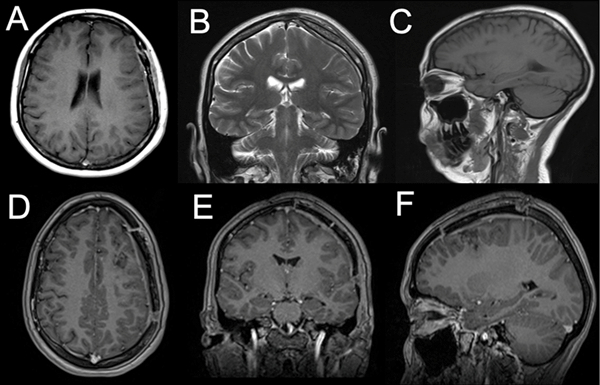

Se efectuó control a los seis meses postquirúrgicos sin evidencia de remanente tumoral ni progresión de la enfermedad (Figura 5). No requirió tratamiento oncológico adyuvante y, al no presentar crisis convulsivas posterior a la intervención, se optó por descender paulatinamente las dosis de anticomiciales hasta su suspensión.

Figura 5. Resonancia magnética cerebral postquirúrgica. A-C) Seis meses posteriores a la intervención, se evidencia la restitución completa del ventrículo lateral izquierdo y del parénquima cerebral circundante, sin evidencia de remanencia tumoral. D-F) No se observan realces patológicos a la administración de contraste endovenoso.